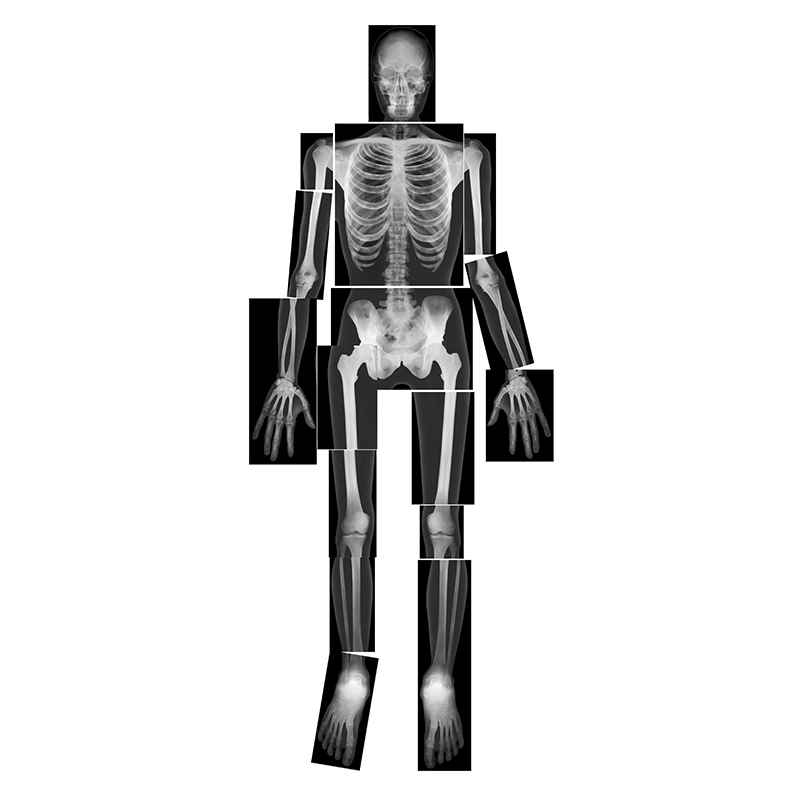

Hold these life-size human x-rays up to the light or use them on a light table and see every authentic detail of a real skeleton. Arrange the 18 pieces together to reproduce the entire body of a young adult 5' (1.5 m) tall. The teacher guide includes reproducible artwork and information on radiography. 18 pieces. Age 5+.